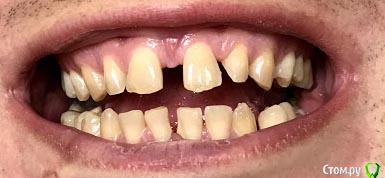

Arkasha18 Опубликовано 4 мая, 2019 Поделиться Опубликовано 4 мая, 2019 (изменено) 35 лет, мужчина.разъезжаются передние зубы все больше и больше, хочу выравнять, насколько ходил по специалистам, все советуют только брекеты.Но остается очень много вопросов по выбору специалиста, т.к. сейчас стоматологов очень много, я не могу выбрать хорошего специалиста, т.к. не разбираюсь в этом. Текущие специалисты меня не устраивают, т.к. допустили уже ряд ошибок которых не должно было быть. Прошу помощи как выбрать специалиста, какие вопросы ему задавать что бы понимать что он специалист хорошо разбирающийся, а не без опытный какой то.набросайте несколько вопросов какие можно задавать пожалуйста. - на например связанные с какими то технологиями, - процессом техническим - варианты брекет систем чем отличаются может что то спросить в общем не знаю..хочется задать вопросы и что бы было понятно кто передо мной, ленивый, знающий, или нет и т.п. если кто то посоветует в питере специалиста на севере города (коменда, старая деревня, пионерская) буду безмерно благодарен И второй вопрос у меня три импланта, верхний на коронке, нижние два без. соот-но придется их снимать? снимки прикрипляю Изменено 4 мая, 2019 пользователем Arkasha18 Ссылка на комментарий